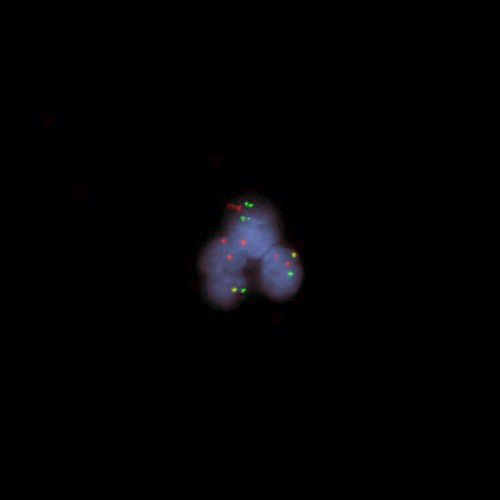

Hybridization of DEK/NUP214 Fusion Probe to a positive cell line showing a fusion due to t(6;9).

The chromosomal translocation t(6;9) (p22;q34) is associated with a specific subtype of acute myeloid leukemia (AML) and constitutes 0.5% to 4% of all AML cases. The translocation results in a fusion between the DEK oncogene (6p22) and the nucleoporin 214 kDa (NUP214 at 9q34; previously known as CAN). The exact mechanism by which the fusion protein DEK-NUP214 contributes to leukemia development has not been identified. Patients with t(6;9) AML have a very poor prognosis. The DEK/NUP214 t(6;9) specific FISH probe has been optimized to detect the reciprocal translocation t(6;9) in a dual-color, dual-fusion assay on metaphase/interphase spreads, blood smears and bone marrow cells.